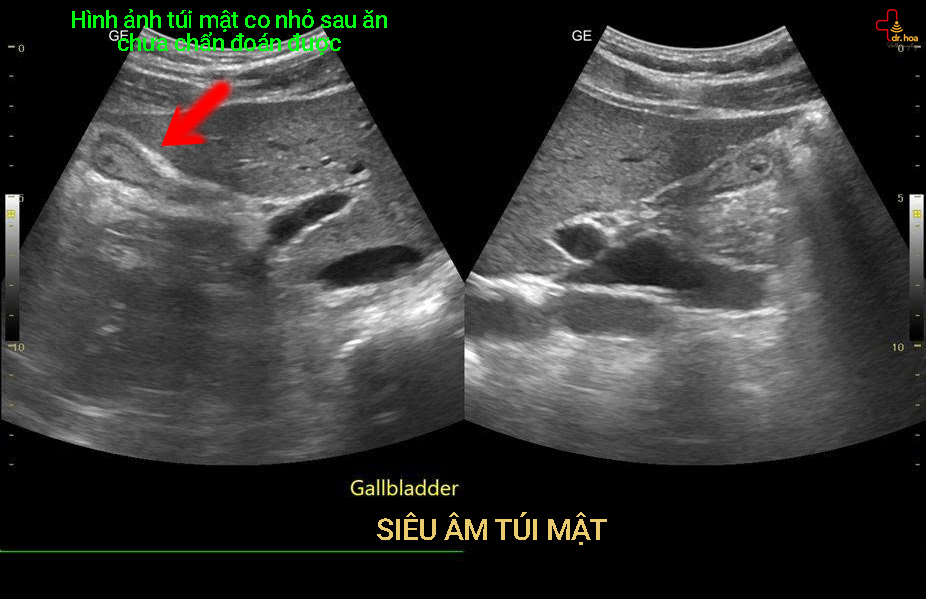

2. Bệnh lý túi mật và đường mật.

Siêu âm tổng quát là phương pháp ưu tiên hàng đầu trong việc khảo sát túi mật.

Các bệnh thường gặp:

- Sỏi túi mật: hình ảnh tăng âm kèm bóng cản âm phía sau

- Polyp túi mật: khối nhỏ dính thành túi mật

- Viêm túi mật: thành túi mật dày, có thể kèm dịch

- Giãn đường mật: gợi ý tắc mật

👉 Siêu âm bụng tổng quát là phương pháp hàng đầu trong phát hiện sỏi mật.

5. Siêu âm bụng tổng quát có cần nhịn ăn không?

👉 Có – trong một số trường hợp.

Khuyến cáo:

- Nhịn ăn 6 – 8 giờ trước khi siêu âm bụng tổng quát

- Tránh đồ uống có gas

- Uống nước nhiều nếu cần siêu âm khảo sát bàng quang.

👉 Điều này giúp:

- Túi mật căng giúp dễ quan sát

- Giảm hơi trong ruột giúp cho hình ảnh quan sát được rõ hơn.